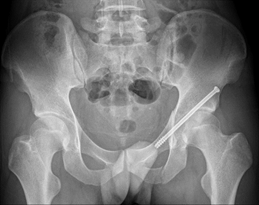

患者是一位24岁的青年男性,外伤导致髋臼骨折。如果常规手术治疗,需要一个很大的切口,钢板螺钉固定创伤较大,所以吴超团队选择使用天玑Ⅱ骨科机器人联合虚拟增强显示技术(AR辅助手术。此次手术吴超团队采用闭合复位、微创的方式,使患者获得很好的功能复位效果,手术切口仅有1.5公分左右,创伤很小。

患者术后情况良好。术后第一天就可以在床上进行不负重的功能锻炼,术后第三天在助行器辅助下已经可以下床行走。

术后X线片和三维CT重建